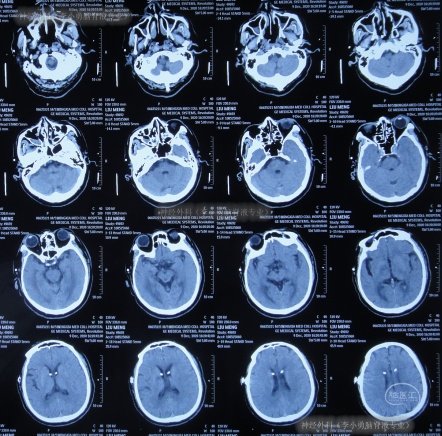

出院后3余年即2020年10月21日,第2次出现行走不稳,头晕;于是第2次就诊给予脑室腹腔分流术的医院,就诊期间出现嗜睡,查头颅CT(图-1)后给予调高分流泵压。

图-1:2020年10月21日头颅CT